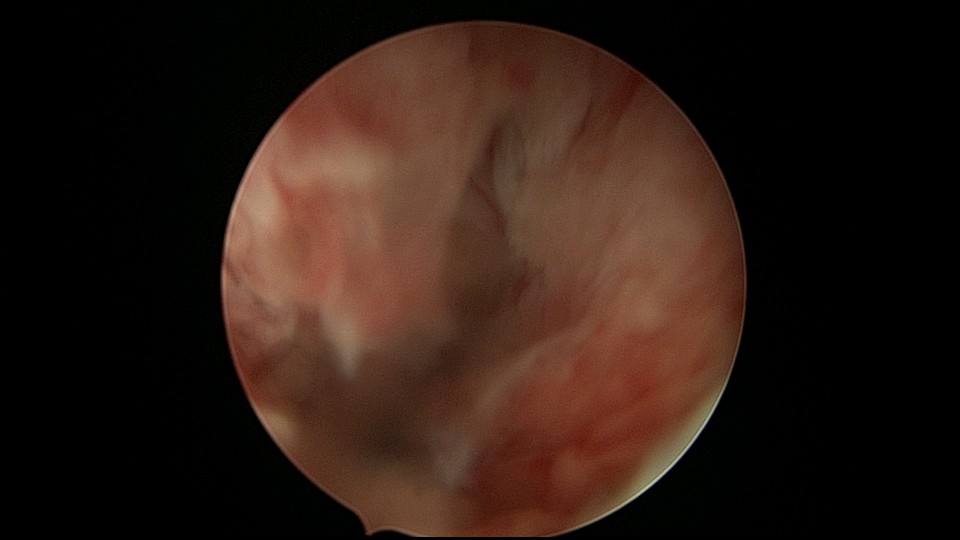

患者48岁,G3P1,顺产1次。安环10年,绝经1年,外院取环失败,子宫穿孔,腹部平片无异常。宫腔镜见宫腔广泛致密粘连,V型环与粘连组织嵌顿,取环钩盲视下多次尝试钩取节育环,均失败。取环钩循镜鞘外侧进入宫腔,直视下钩住节育环,顺利取出。再次置镜寻找子宫穿孔处并进入盆腔,见网膜脂肪组织,确认无活动性出血及盆腔积血,结束手术。